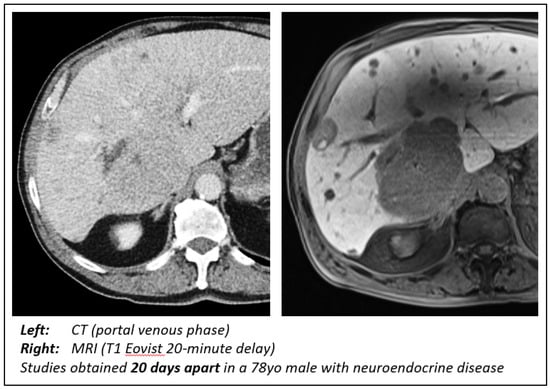

Defining MRI Superiority over CT for Colorectal and Neuroendocrine Liver Metastases